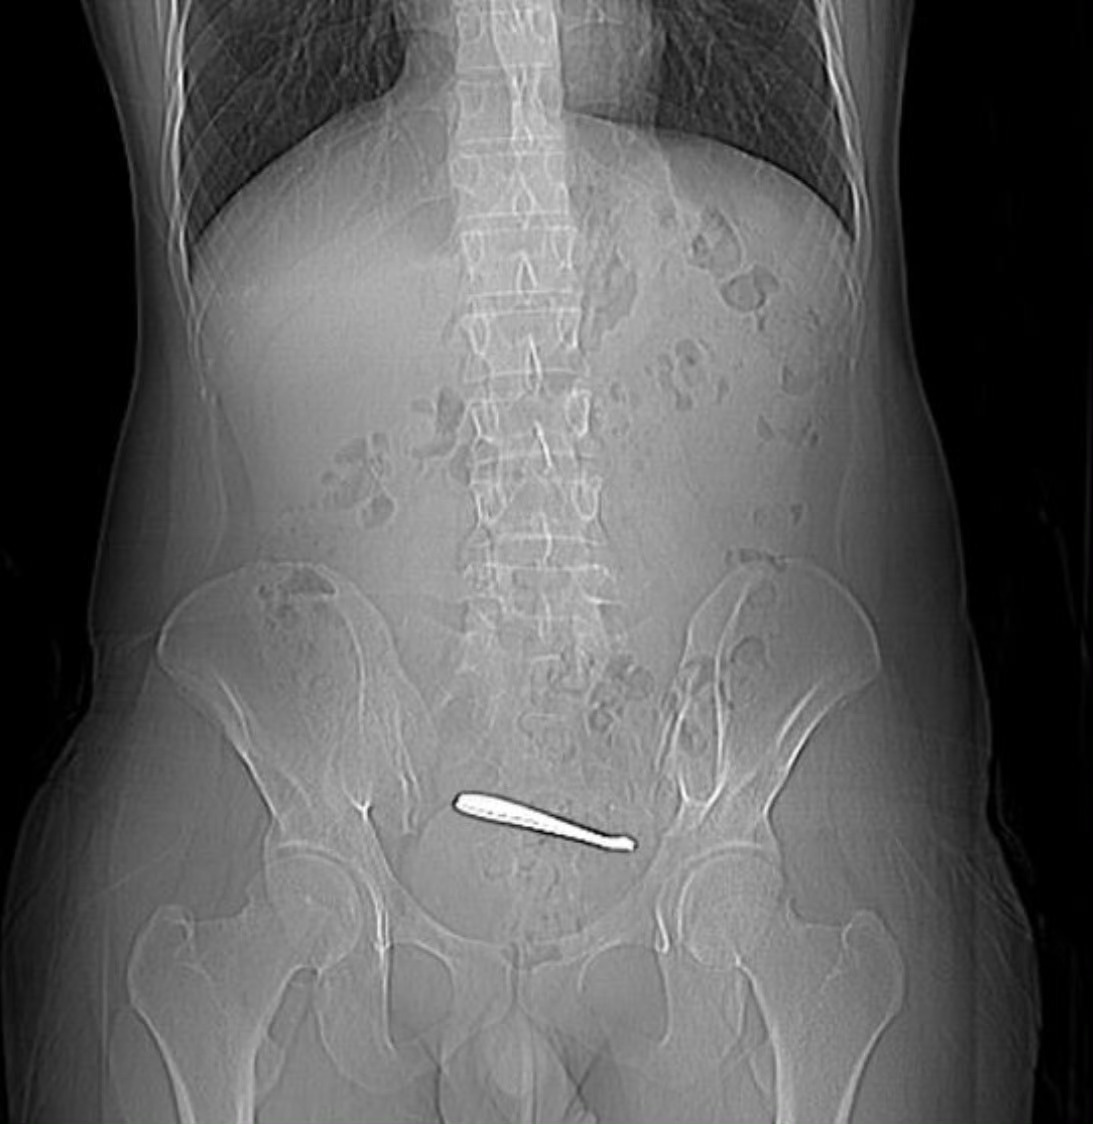

男子肚子疼查出肠道里有勺子,医生花了近一小时才取出来,好奇怎么吞进去的。小伙腹痛

男子肚子疼查出肠道里有勺子,医生花了近一小时才取出来,好奇怎么吞进去的。小伙腹痛CT查出肠道卡2把勺子